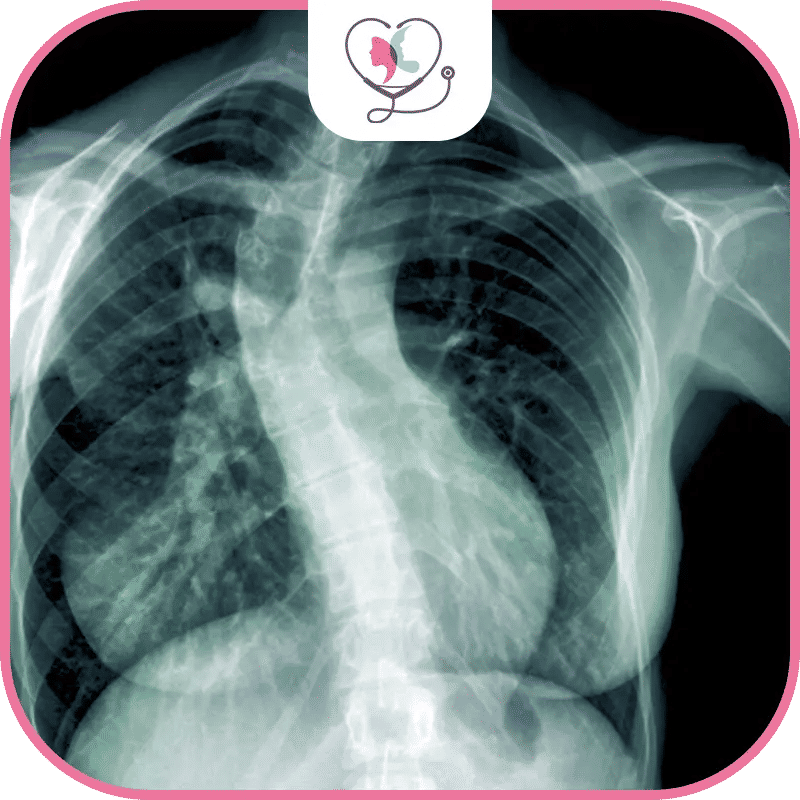

صور قبل وبعد جراحة الجنف في تركيا تحت أيدِ الطبيب همام باقي الغني عن التعريف: